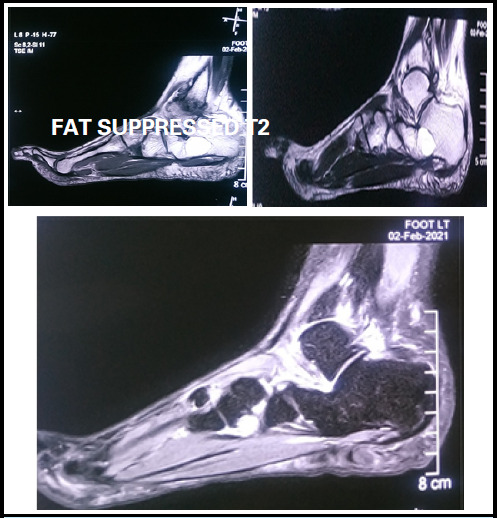

摘要:骨内脂肪瘤是导致足跟疼痛的罕见原因。钙骨是骨内脂肪瘤的典型受累部位。关于小跟骨内脂肪瘤的发表文章寥寥无几,其中一篇来自尼泊尔。我们报告了一例 35 岁女性病例,患者左足跟痛 1 年。疼痛逐渐加剧,严重到无法进行日常生活活动。她接受了刮除手术,并用骨水泥填充了缺损处。在 2.5 年的随访中,没有发现残余疼痛。我们简要回顾了骨内脂肪瘤的假设发病机制、临床表现、诊断和各种治疗方法。骨科医生应高度怀疑足跟痛的罕见病因及其可能的治疗方法。当保守方法不能缓解症状时,手术切除并用骨水泥填充缺损处可长期缓解症状。

Abstract: Intraosseous lipoma of calcaneum is a rare cause of heel pain. Calcaneum is a typical site of involvement of IOL. There are only a few published articles regarding calcaneal intraosseous lipoma and one has been reported from Nepal. We report a case of 35 years female who presented with left heel pain for 1 year. The pain was gradually increasing in intensity and was severe enough to refrain her from activities of daily living. She was surgically operated with curettage and filling the defect with bone cement. There is no residual pain at 2.5 years follow up. We briefly review the postulated pathogenesis, clinical manifestations, diagnosis and various modalities of treatment of intraosseous lipoma. An orthopedic surgeon should have high degree of suspicion regarding the uncommon cause of heel pain and its possible management. When conservative methods do not relieve symptoms, surgical excision and filling the defect with bone cement provides long term relief.